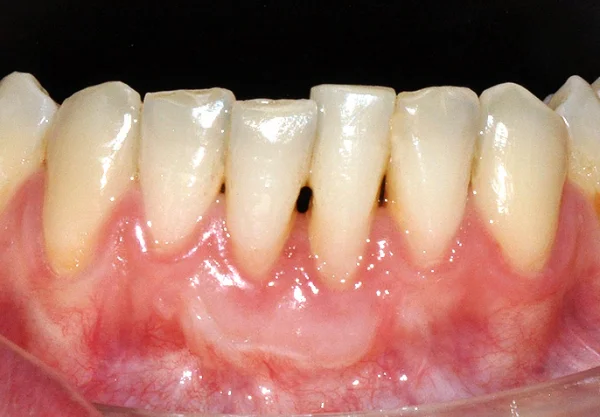

• Encías retraídas o “dientes más largos”.

• Sensibilidad dental por exposición de raíz.

problema encía retraida